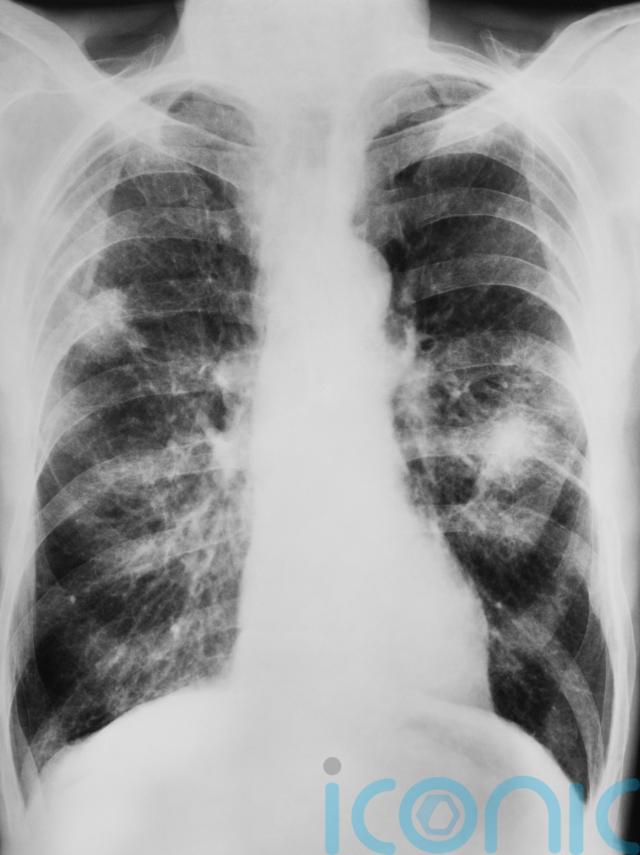

Study suggests link between ultra processed foods and lung cancer

Academics have found a link between consuming high levels of ultra processed foods (UPFs) and lung cancer.

People who consumed the highest amounts of UPFs were 41% more likely to develop lung cancer compared with those who consumed the least amount, academics wrote in the journal Thorax.

Commenting on the study, Professor Sam Hare, consultant chest radiologist at the Royal Free London NHS Trust, said: “A quarter of lung cancer cases occur in non-smokers so we do need research exploring whether other factors are associated with lung cancer.